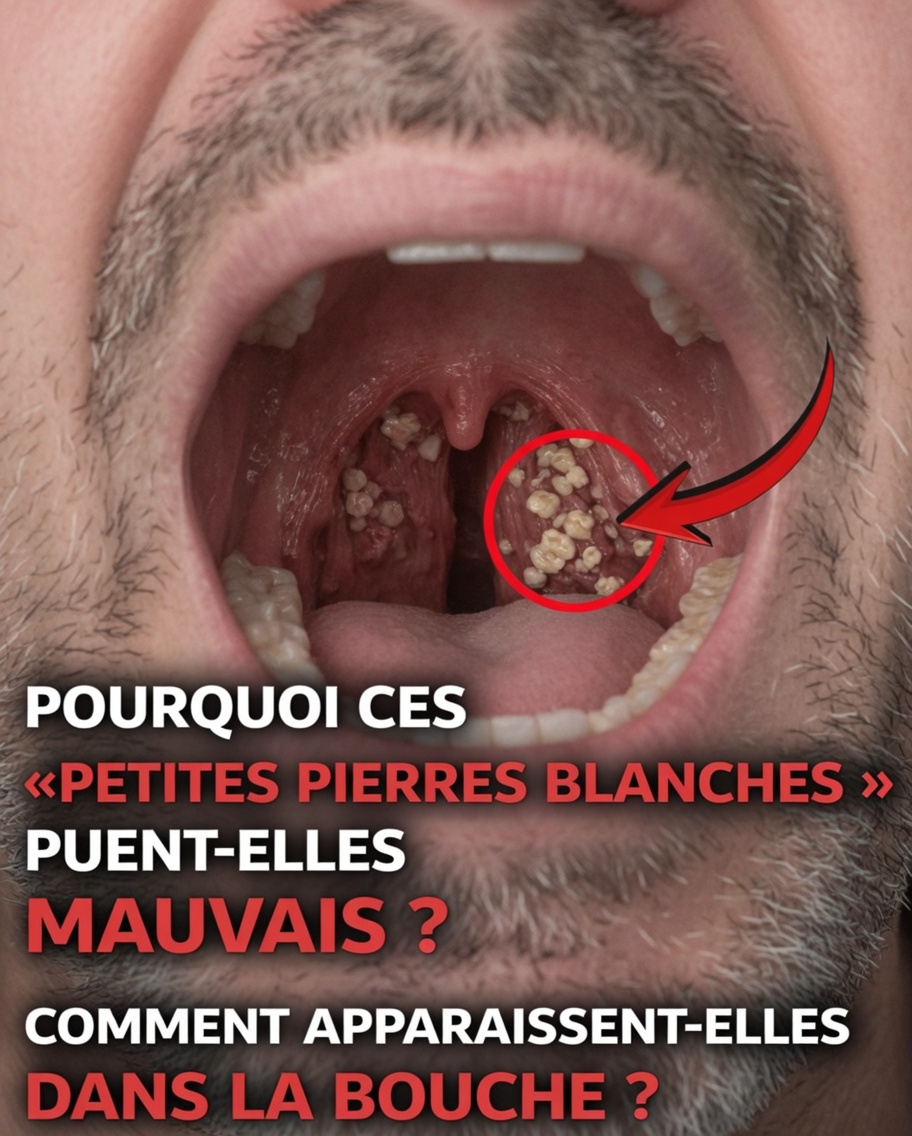

Calculs amygdaliens : ces petites masses blanches qui sentent mauvais

Les calculs amygdaliens (ces petites boules blanches, parfois expulsées en toussant) peuvent être à la fois gênants et inconfortables. Ils sont fréquents et généralement sans gravité, mais leur odeur forte peut rapidement devenir embarrassante en société. Beaucoup de personnes en ont sans le savoir… jusqu’au jour où elles les remarquent. À partir de là, mieux vaut comprendre le phénomène et agir.

Qu’est-ce qu’un calcul amygdalien ?

Les calculs amygdaliens (ou tonsillolithes) sont de petits dépôts durs, souvent blanchâtres, qui se forment dans les amygdales à l’arrière de la gorge. Les amygdales jouent un rôle dans la défense contre les infections, mais elles possèdent aussi des cryptes (petits replis et cavités) où peuvent s’accumuler :

Avec le temps, cet amas se compacte, puis se calcifie (dépôts de minéraux comme le calcium), formant un « caillou » plus ou moins visible.

La taille varie : certains ressemblent à un grain de riz, d’autres à une petite bille. Les plus petits passent inaperçus, tandis que les plus gros peuvent irriter la gorge ou être visibles au miroir.